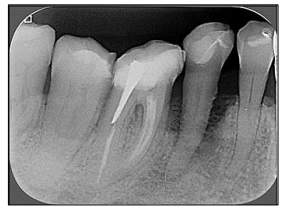

Observe a imagem radiográfica a seguir:

(Mallya, Sanjay M. White & Pharoah Radiologia Oral – Princípios e Interpretação.)

Em qual dos dentes foi realizado um tratamento endodôntico?